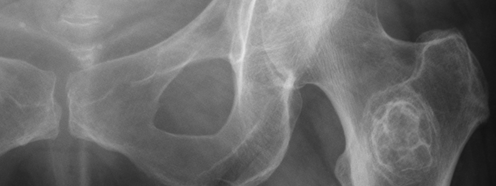

While there is now a well-established link between bone building and calcium supplementation, at the time this article was written the connection was less sure. This article summarizes the relationship between supplementing with calcium and its incorporation into skeletal bone.